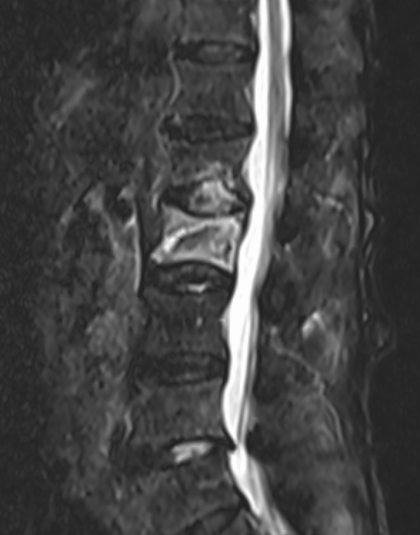

术后

术后

术前

术前